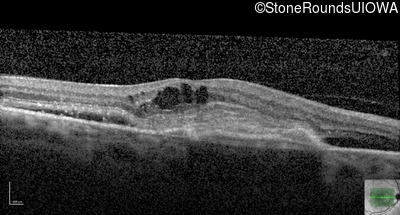

AR Stargardt Disease (IIA)

Age at visit: 59 years (Visit 3)

This 59 year old woman first noticed vision loss in her right eye a few months earlier. She has a cousin with Rhodopsin-associated RP.

Diagnosis & molecular findings

Disease Gene Allele 1 variant(s) Allele 2 variant(s) Inheritance mode

AR Stargardt Disease ABCA4 Arg219Thr AGA>ACA Gly863Ala (G)GA>(G)CA AR